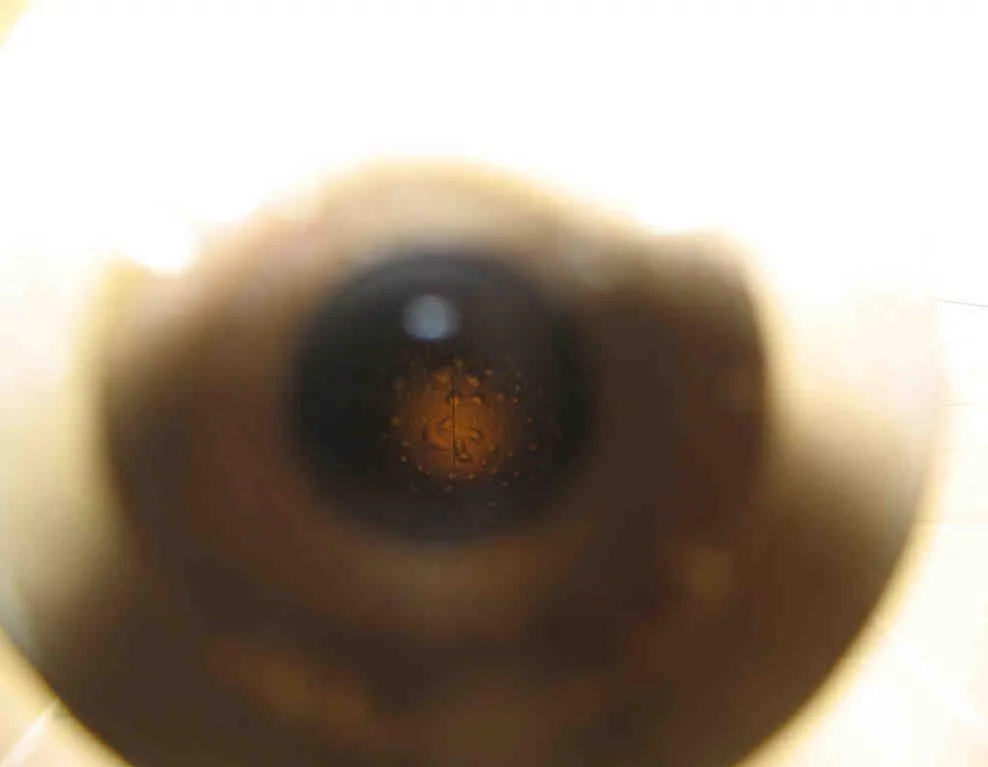

L’un des lecteurs du Portail nous a contacté : il possède deux objets ayant semble-t-il fait partie d’un sous-marin (l’un d’entre eux est un périscope). Il souhaiterait savoir de quoi il s’agit exactement et sur quel type de sous-marins ils étaient embarqués.

Le premier objet, un périscope ?

Le deuxième ...

Merci de bien vouloir déposer vos suggestions en répondant sur le forum.